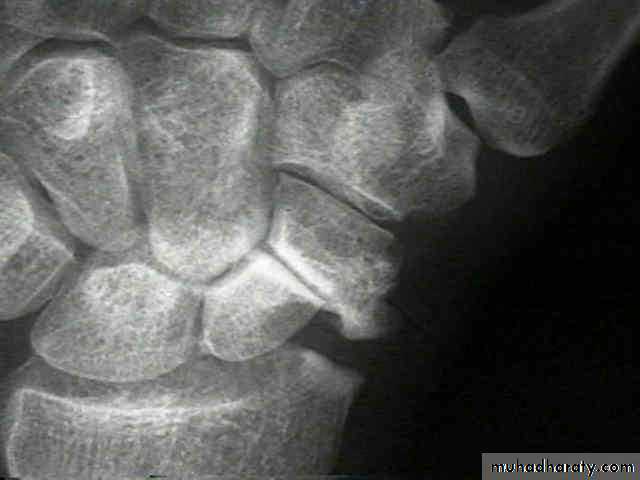

X-ray

Anteroposterior, lateral and oblique views are all essential; often a recent fracture shows only in the oblique view. Usually the fracture line is transverse,and through the narrowest part of the bone (waist), but it may be more proximally situated (proximal pole fracture). Sometimes only the tubercle of the scaphoid is fractured.Treatment